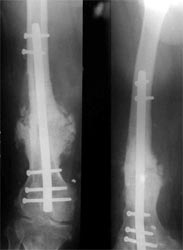

骨髓细胞与骨折愈合:骨髓中骨祖细胞可转化为成骨细胞,具有促进骨修复的作用,应用于临床也取得满意的效果。用髓内钉固定后保证早期稳定性,植骨补充成骨所需基质,骨髓骨祖细胞,可分化成为骨痂组织,骨生长因子促进骨折处再血管化,促进了骨不连的愈合。 病例介绍 病例一、患者63岁,股骨髁上骨折骨不连10年,曾先后4次手术,均采用钢板固定均松脱或折断而失败。 我们采用逆行髓内钉内固定,以及骨髓细胞复合生长因子植骨术,术后1年X线片连续性骨痂形成,膝关节功能良好。

病例二、患者33岁,股骨髁上骨折骨不连2年,曾用Ender’s钉固定断端不稳定,抗旋转性不足,钉移位退出失去固定作用而失败。我们采用逆行髓内钉内固定,以及骨髓细胞复合生长因子植骨术,术后1年X线片连续性骨痂形成,膝关节功能良好。